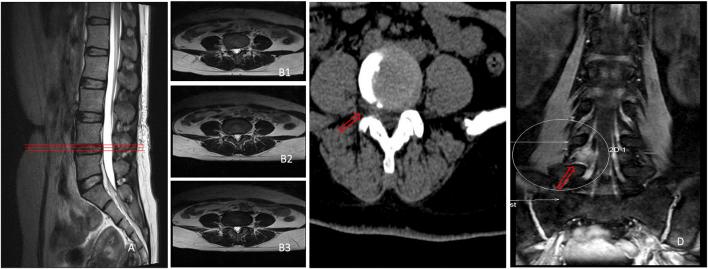

The aim of this study was to explore the significance of three-dimensional double-echo steady-state (3D-DESS) sequence and multidetector computed tomography (CT) plain scan in the diagnosis of lumbar disc herniation (LDH) remaining controversial in conventional magnetic resonance imaging (MRI), and to compare the efficiency between 3D-DESS and CT in diagnosing controversial patients by conventional MRI. A total of 61 patients with controversial LDH diagnosed by conventional MRI were collected. Before operation, the disease of these patients was further confirmed by 3D-DESS sequences and continuous CT plain scan from L3 to S1. Finally, for patients whose postoperative curative effect was marked and symptoms were obviously alleviated, the sensitivity, specificity and accuracy. Among, 59 patients with remarkably relieved symptoms after operation were included, and 2 patients with varying degrees of non-remission of pain and partial dysfunction after operation were excluded. The sensitivity, specificity and accuracy of 3D-DESS were 94.6, 100 and 94.9%, respectively, and those of CT were 75.0, 33.3 and 72.9%, respectively. 3D-DESS is a very useful diagnostic method for patients with some special types of LDH that remain controversial in conventional imaging diagnostic methods. Through 3D-DESS, the morphology of lumbosacral nerve roots can be directly observed, which is conducive to the improvement of the sensitivity, specificity and accuracy, thus further reducing the misdiagnosis rate. Moreover, 3D-DESS plays a guiding role in the formulation of operative methods.

本研究旨在探讨三维双回波稳态(3D-DESS)序列和多排螺旋计算机断层扫描(CT)平扫在常规磁共振成像(MRI)中仍存在争议的腰椎间盘突出症(LDH)诊断中的意义,并比较3D-DESS和CT在通过常规MRI诊断存在争议患者方面的效率。共收集了61例经常规MRI诊断为存在争议的LDH患者。术前,通过3D-DESS序列以及从L3至S1的连续CT平扫对这些患者的病情进行进一步确认。最后,对于术后疗效显著且症状明显缓解的患者,评估其敏感性、特异性和准确性。其中,纳入了59例术后症状明显缓解的患者,排除了2例术后疼痛不同程度未缓解且存在部分功能障碍的患者。3D-DESS的敏感性、特异性和准确性分别为94.6%、100%和94.9%,CT的敏感性、特异性和准确性分别为75.0%、33.3%和72.9%。对于一些在传统影像诊断方法中仍存在争议的特殊类型LDH患者,3D-DESS是一种非常有用的诊断方法。通过3D-DESS,可以直接观察腰骶神经根的形态,有利于提高敏感性、特异性和准确性,从而进一步降低误诊率。此外,3D-DESS在手术方法的制定中发挥着指导作用。